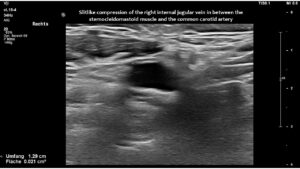

However, in this patient, both jugular veins were compressed. The middle portion of the internal jugular vein was pushed ventrally by the increased cervical lordosis on both sides, becoming squeezed between the carotid artery and the sternocleidomastoid muscle.